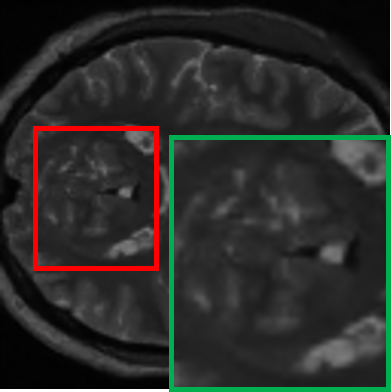

TABLE VII: Clinical evaluation for MS case

Real 3T MRI Real 7T MRI 7T-like SR MRI (3T to 7T)

[Uncaptioned image] [Uncaptioned image] [Uncaptioned image]

In another case involving a patient with multiple sclerosis (MS), characterized by periventricular and subcortical white matter abnormalities. MS lesions, often appearing as small “dark holes” in the brain on T1w MRI, are notoriously difficult to identify on lower-field MRIs. As shown in Table VII, the real 7T MRI provided a significant improvement in resolution compared to the 3T MRI, enabling clearer visualization of MS-related changes in the periventricular regions, which highlights the importance of 7T MRI in detecting subtle lesions. By applying our student model to super-resolve the 3T MRI into a 7T-like quality, the resulting SR image closely matched the real 7T MRI, markedly improving the depiction of the periventricular white matter, making the small “dark holes” indicative of MS lesions much more apparent.